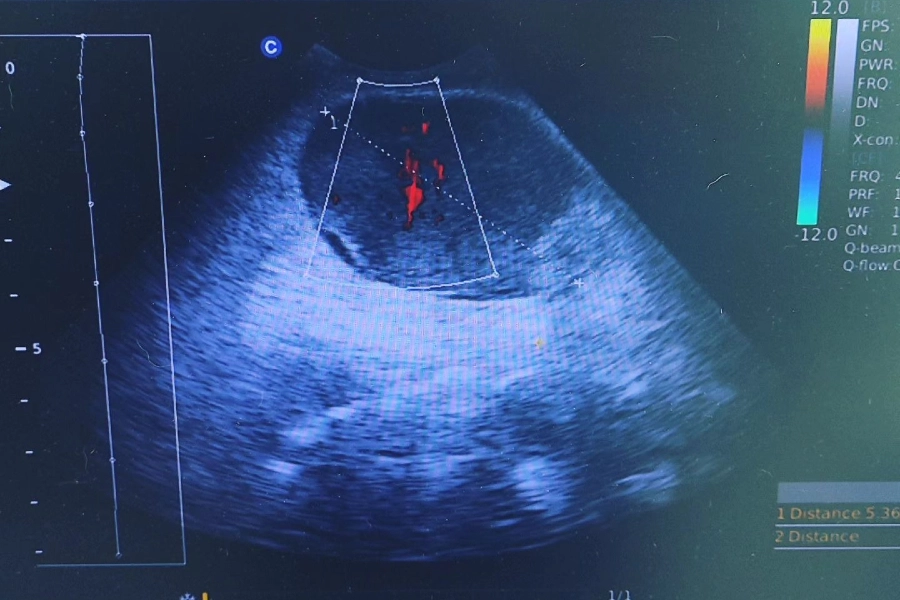

Ο Καμπούρης Ιωάννης είναι Κτηνίατρος και διατηρεί ιδιωτικό κτηνιατρείο στην Καλλιθέα. Είναι απόφοιτος της Κτηνιατρικής Σχολής. Στον χώρο του κτηνιατρείου του, παρέχονται ολοκληρωμένες κτηνιατρικές υπηρεσίες για τους μικρούς φίλους, με έμφαση στη φροντίδα, την πρόληψη και τη θεραπεία. Πραγματοποιούνται χειρουργικές επεμβάσεις, ακτινογραφίες, ενδοσκοπήσεις, καθώς και υπερηχοτομογραφικές αναλύσεις για την ακριβή διάγνωση παθολογικών προβλημάτων. Επιπλέον, παρέχονται εμβολιασμοί, ηλεκτρονική σήμανση (microchip), οδοντιατρικές πράξεις, καθώς και εργαστηριακές εξετάσεις αίματος και ούρων, με στόχο την πλήρη και υπεύθυνη φροντίδα κάθε κατοικιδίου. Το κτηνιατρείο καλύπτει υπεύθυνα κάθε ανάγκη φροντίδας των ζώων συντροφιάς, προσφέροντας υπηρεσίες με συνέπεια, επιστημονική γνώση και σεβασμό απέναντι στους μικρούς ασθενείς.